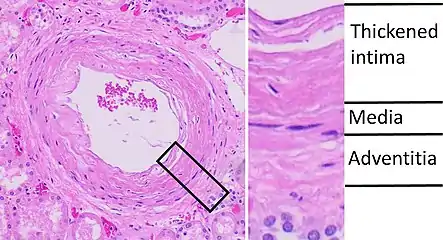

High blood pressure in the long term can damage the endothelium, commonly known as the blood vessel lining. This leads to a build-up of plaques and they can be deposited in the renal arteries causing stenosis and ischemic kidney disease. In this situation, the kidney supplied blood by the narrowed renal artery suffers from inadequate blood flow, which in turn causes the size of the kidneys to decrease. Other consequences include arterial stiffening, which involves a gradual breakdown of elastic fibers and intima (the innermost layer of a blood vessel) thickening.

In benign nephrosclerosis, the changes occurring are gradual and progressive, however, there can be sufficient kidney reserve capacity to maintain adequate kidney function for many years.[10] The large renal arteries exhibit intimal thickening, medial hypertrophy, duplication of the elastic layer. The changes in small arterioles include hyaline arteriolosclerosis (deposition of hyaline, collagenous material), which causes glomerular collapse (wrinkling and thickening of capillary basement membranes and collapse of capillary lumen) and solidification (glomeruli exhibit sclerosis and increase in mesangial matrix). The degree of scarring correlates with the degree of glomerular filtration deficit.

Light micrograph of glomerulus showing secondary segmental sclerosis of hypertensive nephropathy. Histopathology of arcuate artery nephrosclerosis, seen as a thickened intima with an onion skin-like architecture. It is presumably a manifestation of hypertensive kidney disease.

Histopathology of arcuate artery nephrosclerosis, seen as a thickened intima with an onion skin-like architecture. It is presumably a manifestation of hypertensive kidney disease. Light micrograph showing signs of hypertensive nephropathy: interstitial fibrosis, tubular atrophy with thickened tubular basement membranes, and fibrous intimal thickening of a small artery (arrow).

Malignant nephrosclerosis is where hypertensive nephrosclerosis occurs in presence of malignant hypertension (when DBP > 130mmHg).[11] Vessels feature intimal thickening, fibrinoid necrosis, red blood cell fragmentation, extravasation, thrombosis. These changes create an exaggerated layered appearance (onion skinning).[12]